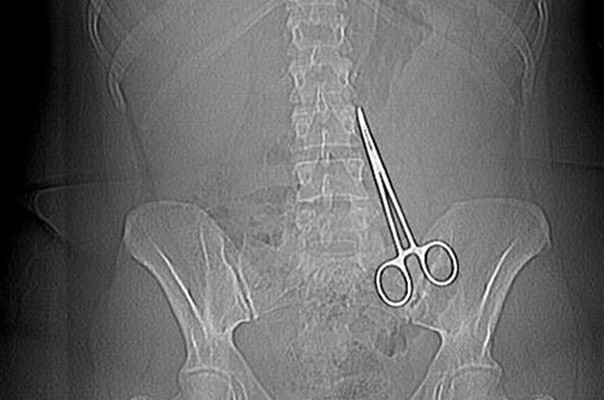

Բժիշկները թուրք կնոջ որովայնում մկրատ են մոռացել, որը հայտնաբերվել է միայն 6 ամիս անց

Գերմանաբնակ Էմել Բինգյոլը, ով որոշել էր պլաստիկ վիրահատության Թուրքիայի Գազիանթեփ քաղաքում, 6 ամիս շարունակ ստիպված է եղել ապրել նժիշկների որովայնի մեջ մոռացված մկրատով, այս մասին գրում է demokrathaber.org կայքը:

Գերմանիայում բնակվող թրքուհին որոշել էր վիրահատվել հայրենիքում՝ առավել մատչելի գների պատճառով: Պարզվում է, որ վիրահատության ընթացքում թուրք բժիշկները մոռացել են հիվանդի որովայնի մեջ բժշկական մկրատ, որը հայտնաբերվել է միայն 6 ամիս անց:

Կինը ստիպված է եղել կրկին վերադառնալ Թուրքիա և նորից վիրահատության ենթարկվել Ուրֆայի հիվանդանոցներից մեկում:

Էմել Բինգյոլն ու իր փաստաբանը պահանջում են նաև բժիշկներից ոչ միայն նյութական, այլև բարոյական փոխհատուցում, քանի որ կինը ստեղծված իրավիճակի պատճռառով խորը սթրես է տարել և ստիպված եղել դիմել հոգեբանի օգնությանը: